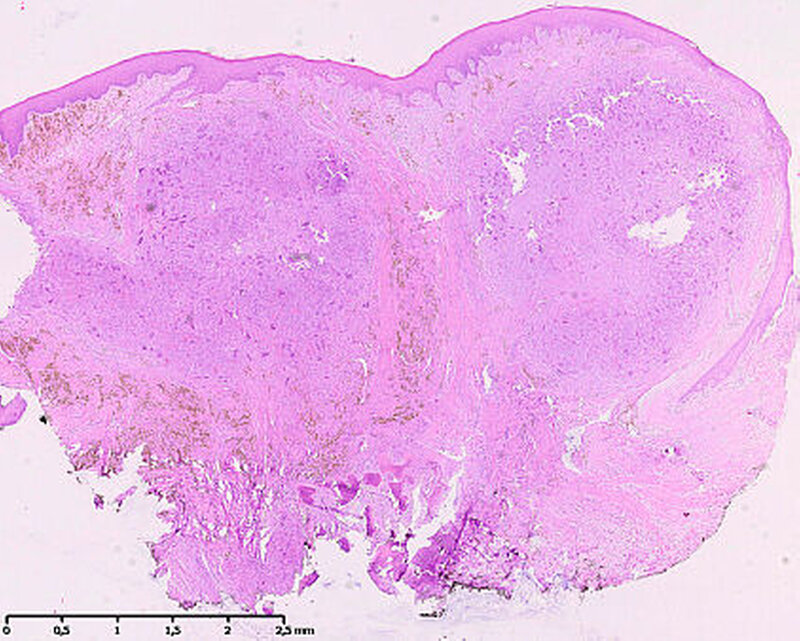

Die histopathologische Untersuchung ergab eine riesenzellbildende Läsion, so dass eine rein histopathologische Unterscheidung zwischen zentralem beziehungsweise peripherem Riesenzellgranulom und einem braunen Tumor nicht möglich war. Die weiterführende laborchemische Diagnostik ergab ein erhöhtes Parathormon im Serum 148,2 pg/ml (Norm: 15,0 bis 68,3 pg/ml) und ein normales Serumkalzium von 2,38 mmol/l (2,20 bis 2,55 mmol/l), so dass in Zusammenschau aller Befunde von einem braunen Tumor bei renal sekundärem Hyperparathyreoidismus auszugehen ist.

Histopathologisch zeigen braune Tumore einen ähnlichen Aufbau wie Riesenzellgranulome beziehungsweise die solide Variante der aneurysmatischen Knochenzyste. Alle zeichnen sich durch das Vorhandensein von gefäßreichem Granulationsgewebe aus, in das zahlreiche mehrkernige osteoklastäre Riesenzellen eingebettet sind [Neville, 2009]. Hämosiderinbeladene Makrophagen führen zur typischen rötlich-braunen Farbe, die dem Tumor den Namen gegeben hat. Differenzialdiagnostisch bedarf es dann der laborchemischen Abklärung, um die Dia-gnose eines braunen Tumors stellen zu können. In der Regel werden Parathormon, Kalzium und Phosphat bestimmt.